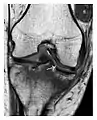

a

b

Figure 7: Fatigue fracture of the talus in a 25-year-old male basketball player with right hind foot and ankle pain, without history of trauma, and a normal initial radiograph (not shown). (a) One-month followup lateral radiograph shows normal appearance. (b) Sagittal T1-weighted MRI shows an irregular fracture line (arrow) within an ill-defined area of hypointensity corresponding to bone marrow edema.[1]